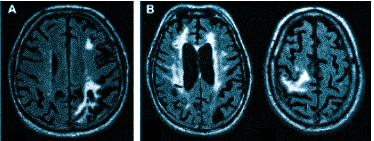

Если делать МРТ, когда не болит голова

Множественные ишемические очаги при сосудистой деменции на МРТ: отсутствие памяти на недавние события и неадекватное поведение не являются признаками старости, своевременная диагностика деменции и патогенетическая терапия помогут замедлить прогрессирование болезни

демиелинизацию при рассеянном склерозе и иных атрофических процессах;

острые (ишемический или геморрагический инсульт) и хронические нарушения мозгового кровообращения.